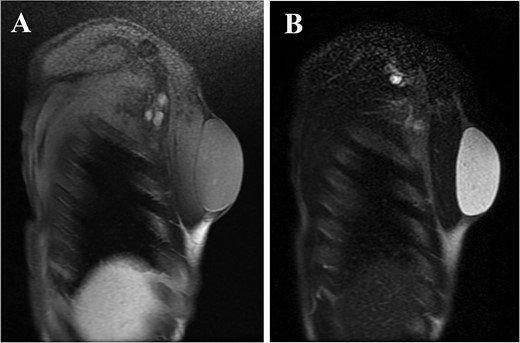

A 61-year-old man presented to the outpatient breast clinic with a painless lump in his right pectoral region. The lump was first noticed 40 years earlier at the size of a small fingertip and gradually increased. The lump was approximately 90 mm in diameter, well-defined, and dome-shaped. The overlying skin appeared glossy with no visible puncta (Fig. 1). Erythema or bruising was not observed. On palpation, the lump was non-tender and doughy with no localized temperature increase. It was not fixed to underlying tissue. On ultrasound imaging, the lump showed a hypoechoic and well-circumscribed oval mass containing variable echogenic foci and filiform anechoic areas without color Doppler signals (Fig. 2). The lump was located in the subcutaneous fat layer, with extensive dermal apposition. In sagittal magnetic resonance imaging (MRI), the lump showed a unilocular and well-defined cystic mass (70 × 40 × 90 mm) (Fig. 3A and B). The cyst content showed an isointense signal relative to the muscle with no enhancement in the sagittal enhanced T1-weighted image (Fig. 3A), and a hyperintense signal in the T2-weighted image (Fig. 3B). Ultrasound-guided percutaneous CNB was performed, and six core specimens containing cystic walls ware sampled (Fig. 4A). The cystic wall was lined with mature stratified squamous epithelium with a granular layer and did not contain an adnexal structure (Fig. 4B). In addition, many laminated or basket-woven keratin layers were sampled. These findings ware consistent with those of an epidermal cyst. The mass was excised under general anesthesia. The mass was well-defined and did not adhere to the surrounding structures, except for a portion of the CNB (Fig. 5). The mass was easily excised. The formalin-fixed mass was covered with a thick white fibrous capsule (Fig. 6A), which was filled with grey substances, such as bean curd residue, in the cross-section (Fig. 6B). After the removal of the contents, the internal surface of the capsule was crepey, and no nodules were observed (Fig. 6C). The definitive pathological diagnosis was an epidermal cyst without any malignancy. The adhesive region revealed keratin, which flowed outside the cyst, and a granulomatous response to keratin with multinucleated giant cells (Fig. 7). No complications or recurrences were observed during the one-year follow-up after surgery.